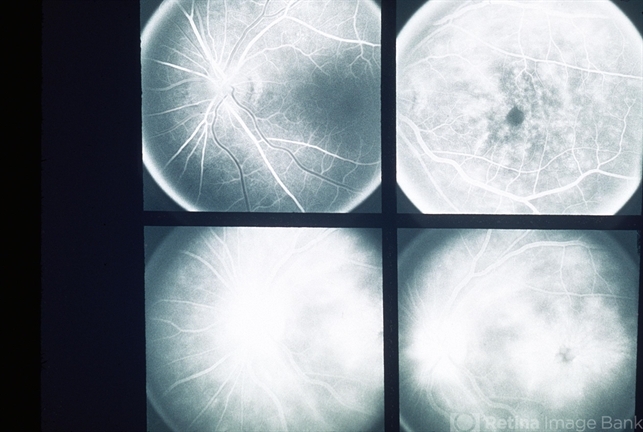

- Harada's disease, cyclitis

- 51-year-old white female, 20/100; Harada's disease, cyclitis.